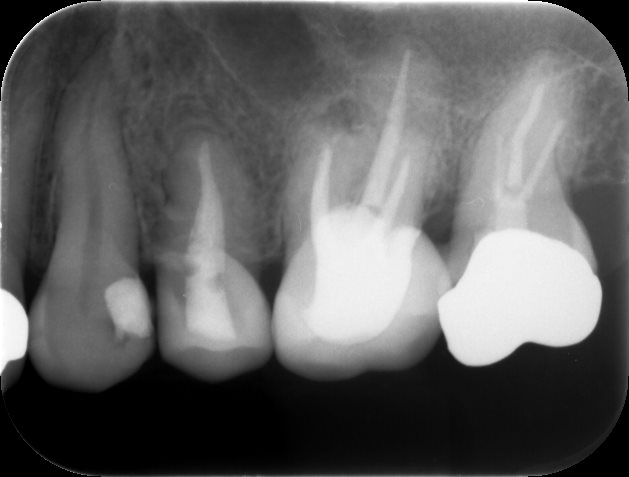

被せ物装着後3ヶ月

被せ物を装着し、6ヶ月が経過した際のレントゲンです。根の先の黒い透過像がなくなっていることがわかります。痛みもなく、経過良好です。